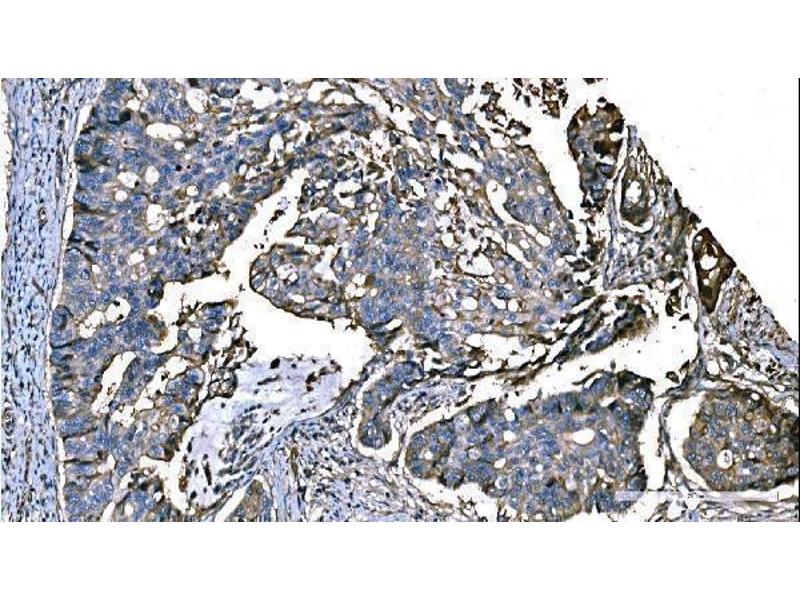

• 图像